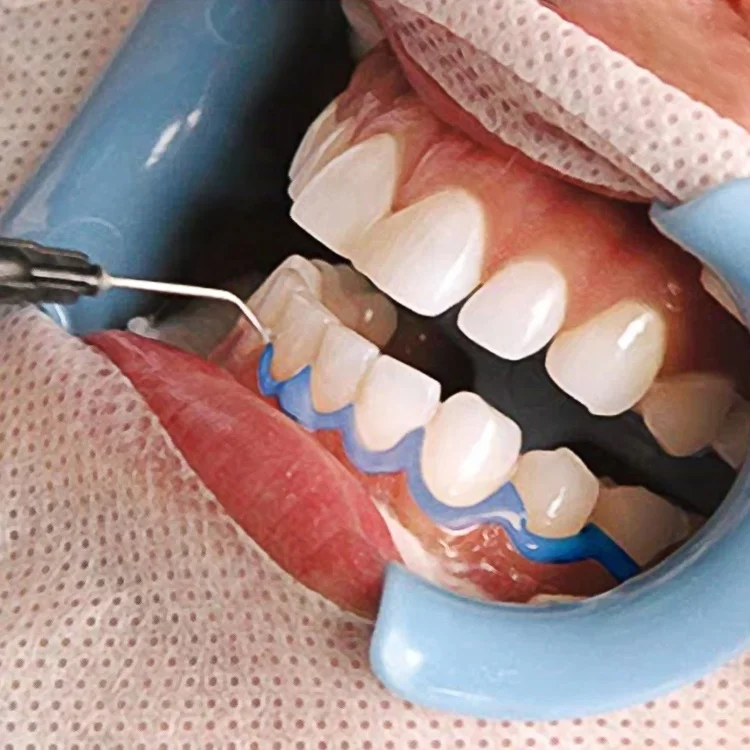

CE Approved 1.5/3ml Home Use Teeth Whitening Gel Gingival Barrier Gum Protective Dental Gum Protector